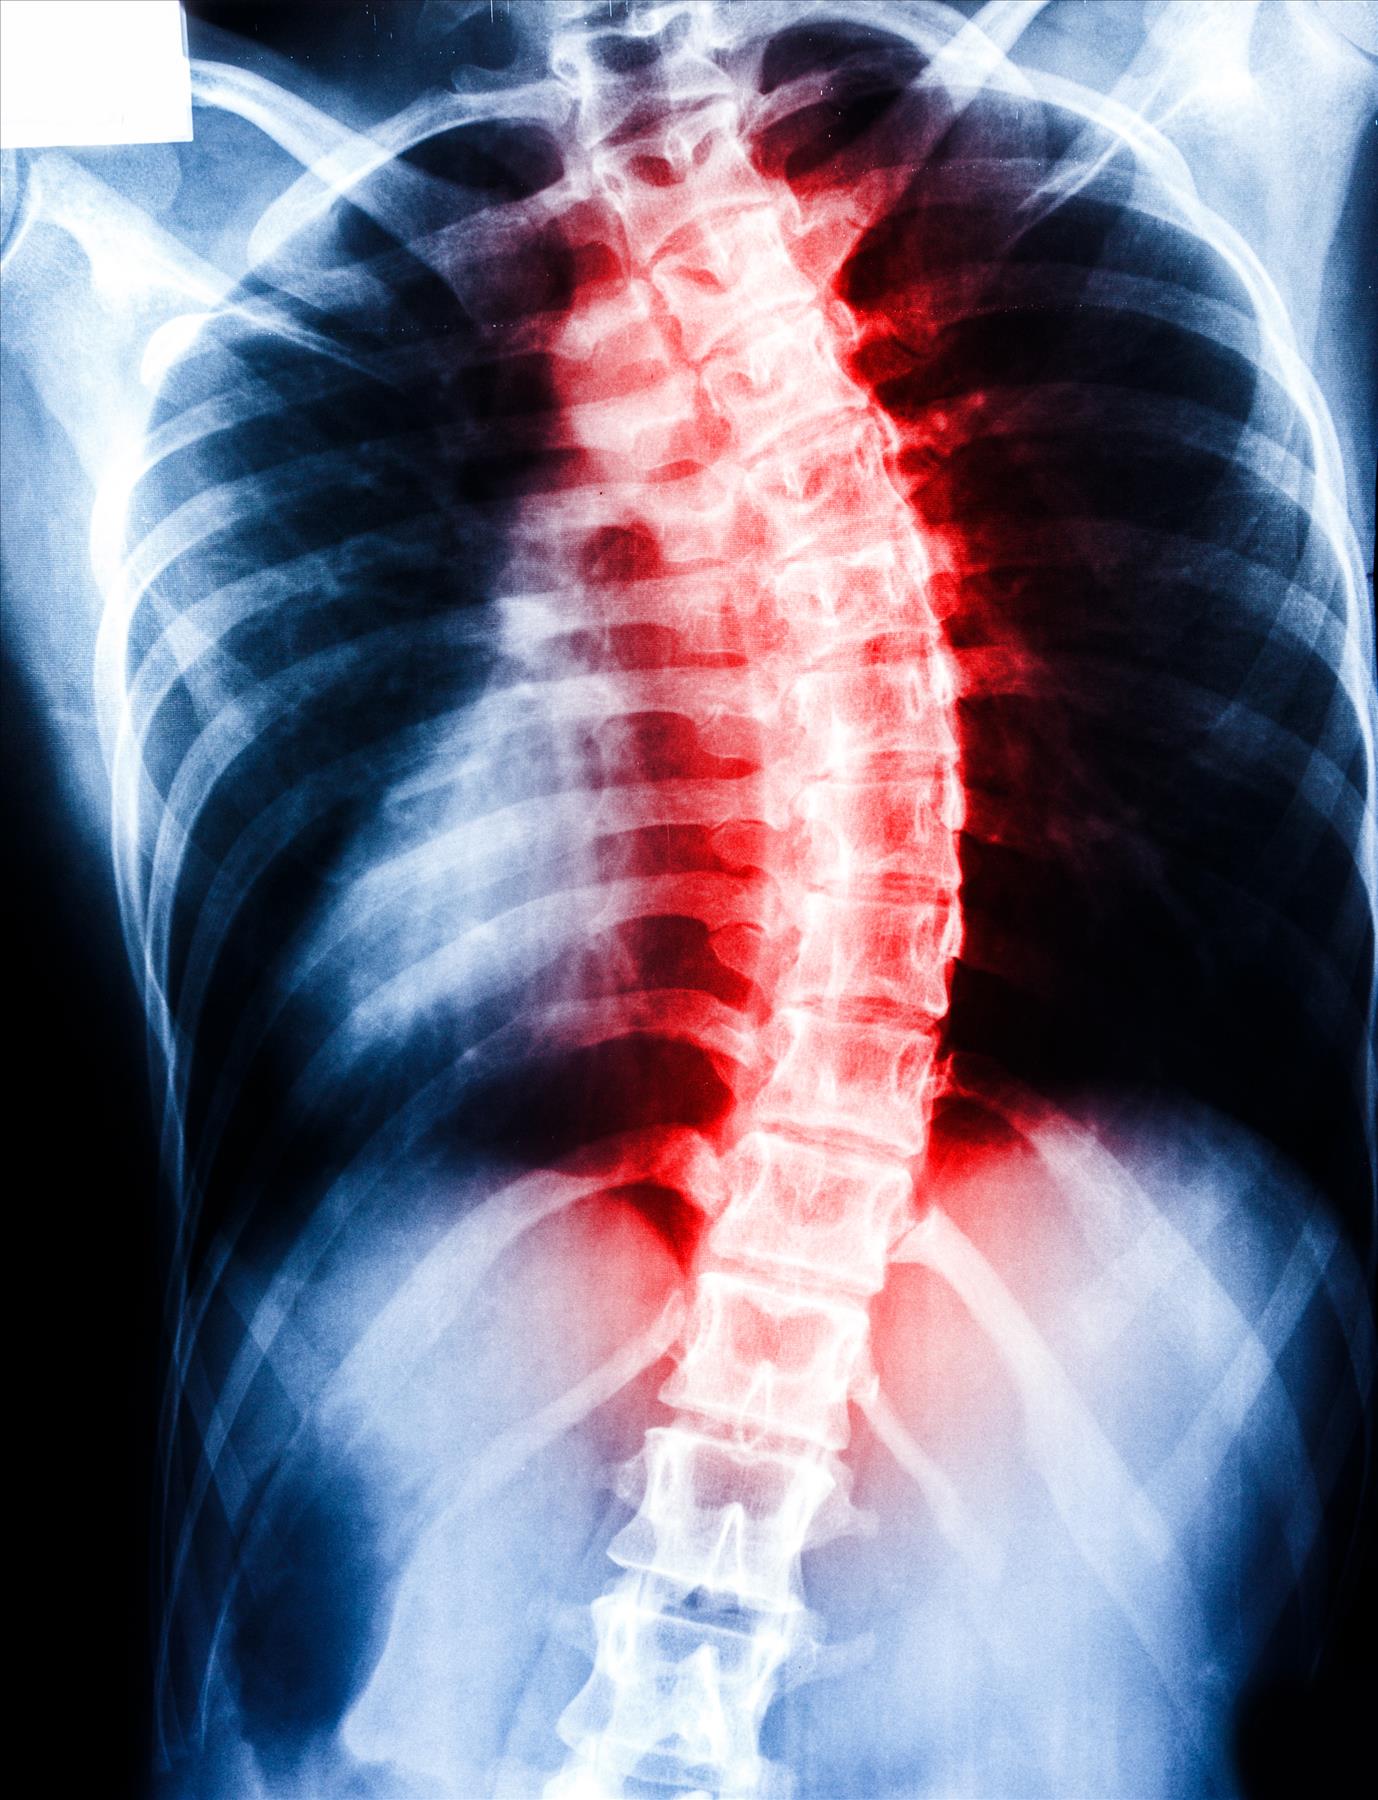

Filing a Spinal Injury Claim after a Complete Injury